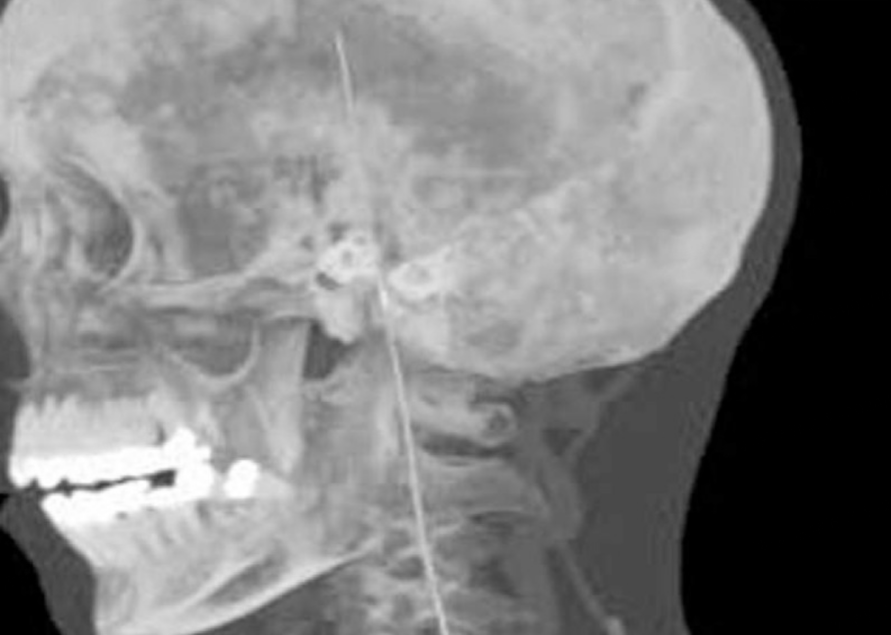

重庆医科大学第一附属医院血管外科曾接诊过一个异物顺着血管到达大脑的病例。该院血管外科在2019年发文称,患者4年前在外院发生导丝血管内丢失,当时手术无法取出。来到该院时,患者已出现脚踝肿胀、头痛症状,检查发现血管内的导丝断成两截,其中一段刺穿血管壁到达大脑。由于手术风险大,患者拒绝手术。

计算机断层扫描三维重建显示,导丝上端已进入大脑位置。

图源/期刊Medicine(Baltimore)